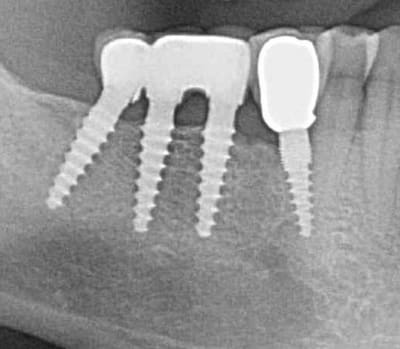

Bonjour flicflac je suis désolé de ma réponse tardive, oui il est vrai que ce n est pas beaucoup documenté ... je serai un menteur de dire que que je n ai jamais perdu des implants, surtout entre la 2eme et 8eme semaine après l implantation.Un échec vraiment à cause de la perte osseuse et avec le même process cela est arrivé une fois avec une madame, où l´os était encore infecté ( avant la chirurgie),mais après l ´échec (c était à la position 35) on a pu laisser le bridge. Malheureusement je n ai pas toutes les photos ici à Mallorque sur mon PC portable. Ci dessous une photo après 10 ans 46 47 et les implants au maxillaire.

Oui ca semble ....sur la opg radio tu peux voir la situation seulement deux semaines après l´implantation immédiate 34 jusqu´à 36 et 45, les derniers 2 photos montrent la même situation après un an ( où on a enlevé la supra construction pour un contrôle). Sur ce cas je voulais montrer la bonne régénération osseuse et de la gencive.

Voilà une patiente que je revois à deux ans apres la pose d'un monobloc Classic line 3,5/12mm et prep cap zircone 12 degres 2/2 en 24.

Radios 1,2,3 photo 1= jour de la pose de l'implant.

radio 4 photo 2 et 3= 8 semaines post pose de l'implant, ceramiques scéllées.

Radio 6, photo 4 et 5 controle à 24 mois.

Deux ans plus tard, la gencive a recouvert la zircone et on observe à la radio un gain osseux au niveau des micros spires.